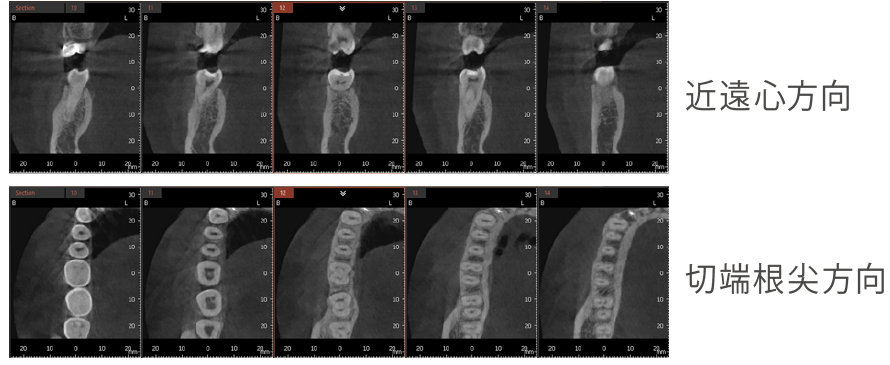

虫歯が大きくて神経をとる治療においては今までのレントゲンでは細かい神経の穴の場所を把握できませんでしたが、CTにより場所を正確に立体化できるため細かい神経の穴の場所を認識しやすくなりました。